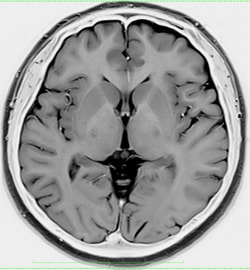

最初に問診を行います。必要に応じて検査を行い、その後、診察/検査結果を説明し方針を立てます。脳神経外科診療においてはMRI検査が頭蓋内評価に有用ですので、診察/診断の根拠のためにもキー写真をスナップショットでお渡しするようにしております。

頭痛/めまいなどは脳卒中や脳腫瘍などの初発症状のこともるため、MRIにて頭蓋内スクリーニングを行います。当日、結果説明します【理念2・4】。